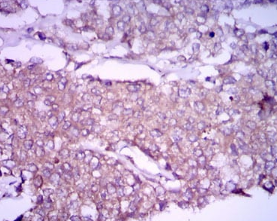

IHC    1/200 - 1/1000